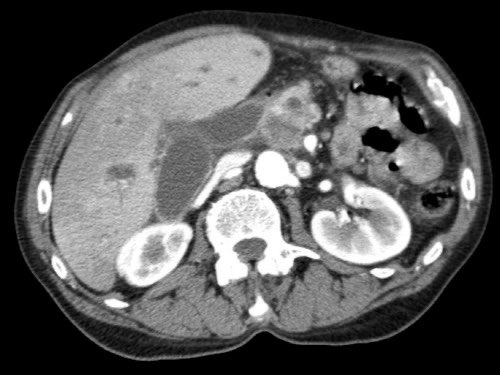

Tái tạo mặt phẳng coronal cho thấy:

- Bất thường bờ viền thành SMV được nhận thấy rõ hơn trên tái tạo coronal này (mũi tên).

- Khối u ở thân tụy (đầu mũi tên trắng).

- Huyết khối trong các nhánh bên của SMV (mũi tên xanh nhỏ).